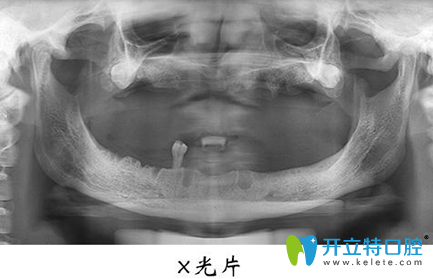

宏沅膛口腔面诊的医生非常细心也很有耐心,我不懂的牙齿问题都会很有耐心的告知我,在牙齿种植术前,需要进行常规的身体检查,拍摄X光片,了解失牙区的骨质和骨量,以确定是否适宜进行牙齿种植等…